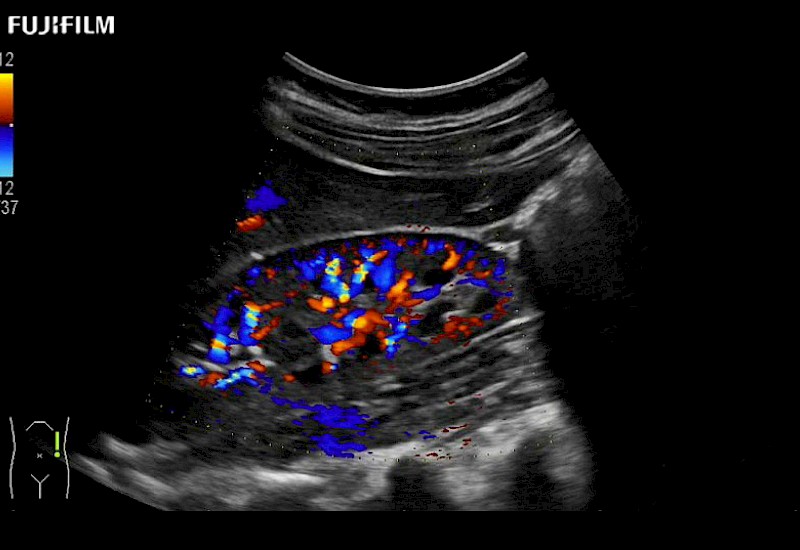

Extraordinary high-resolution digital imaging

Multi-Parametric imaging modalities